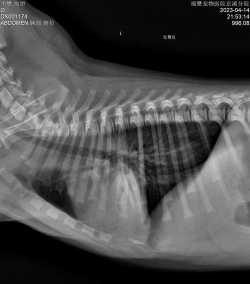

犬的肺部蠕虫感染

狗的肺部蠕虫感染通常是由气管蠕虫Oslerus osleri引起的。它们在美国、南非、新西兰、印度、英国、法国和澳大利亚都有发现。成年肺蠕虫生活在狗气管的结节中,成年肺蠕虫产下的幼虫卵在那里孵化。小狗从受感染狗的粪便或唾液中感染。狗很少感染